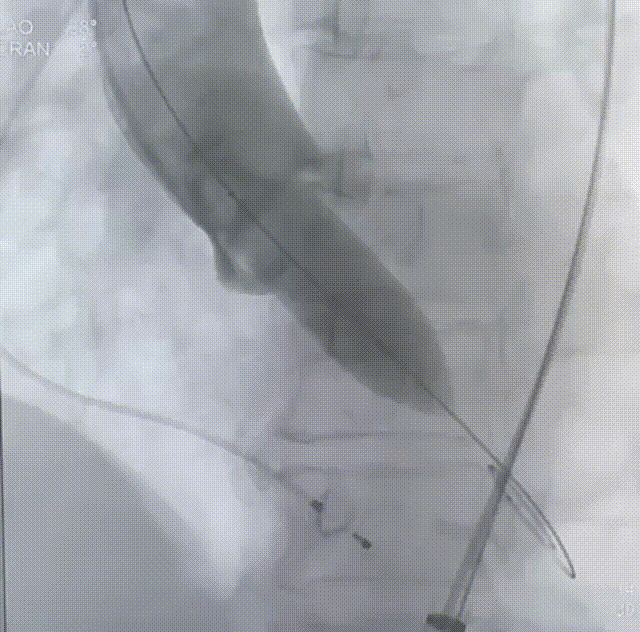

22mm球囊预扩

瓣膜定位

瓣膜释放至75%

瓣膜脱钩

瓣膜完全释放

22mm球囊后扩

完成植入